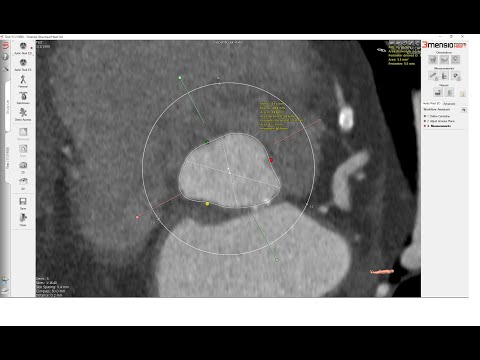

3Mensio CT Pre-case Planning: Redo-TAVR with Prior Sapien 3 (1 of 2)

Sizing the Aortic Valve Annulus 3Mensio